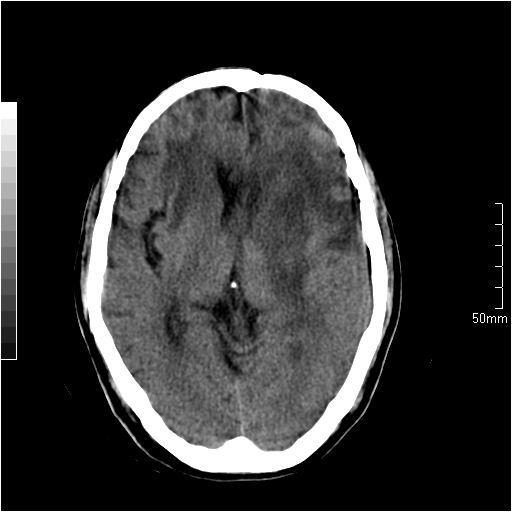

以下是引用天南地北在2007-6-25 12:39:00的发言:[br]有占位效应[br]支持术后复发

以下是引用zjzjr在2007-6-25 12:38:00的发言:[br]左侧复发,右侧转移。